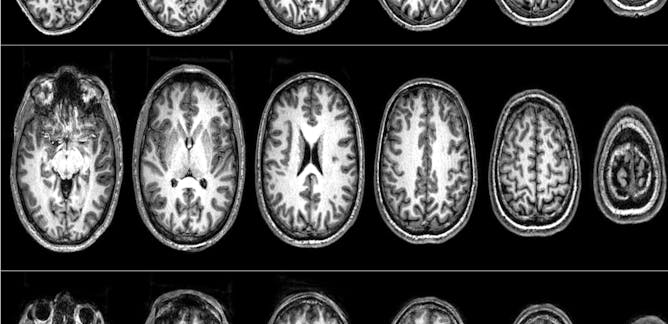

The neuroscience of terrorism: how we convinced a group of radicals to let us scan their brains

Nafees Hamid, UCL; Clara Pretus, Autonomous University of Barcelona

The process of radicalisation is a complex system that cannot be reduced to the brain, behaviour, or environment. It exists at the intersection of all these elements.